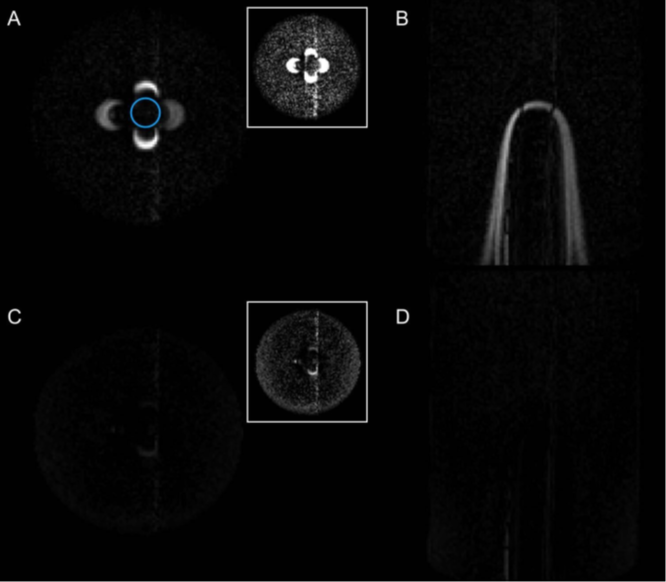

5/9 🧪 Phantom test: Standard FLAIR → large bright artifact near induced inhomogeneity C-FLAIR → signal properly suppressed throughout This demonstrates the core mechanism clearly.